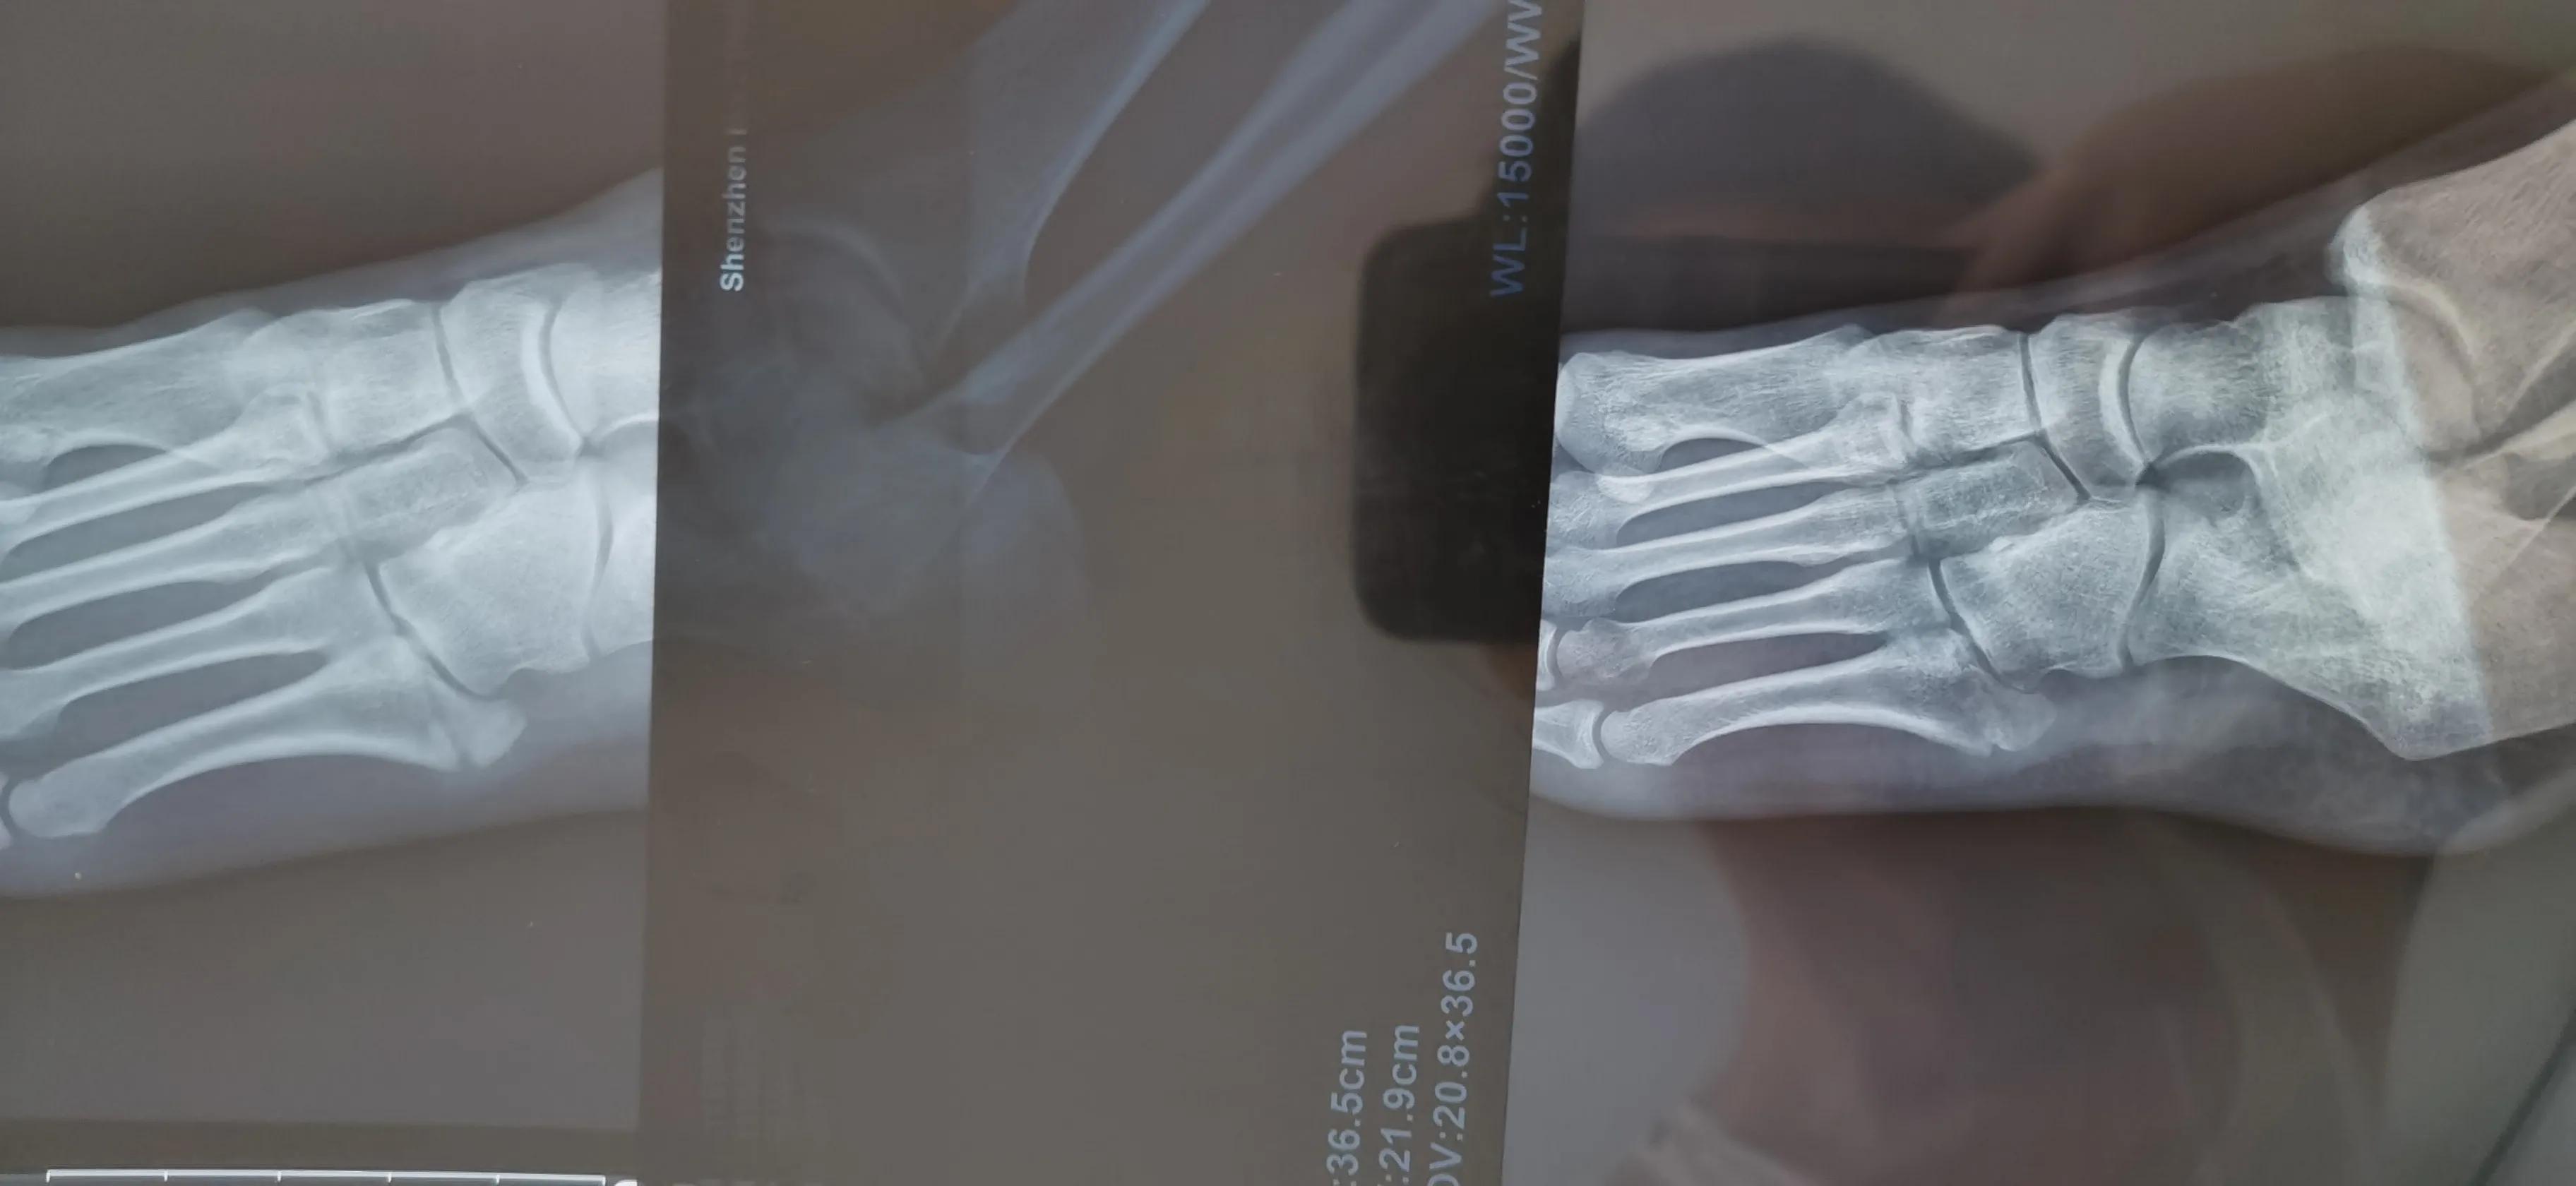

看片子骨缝比较大了,有点移位,而且中间崩碎了一块,一直找不到,后来复查才发现那个碎片掉落在骨缝当中了

此图可以看见中间碎片在骨缝里面